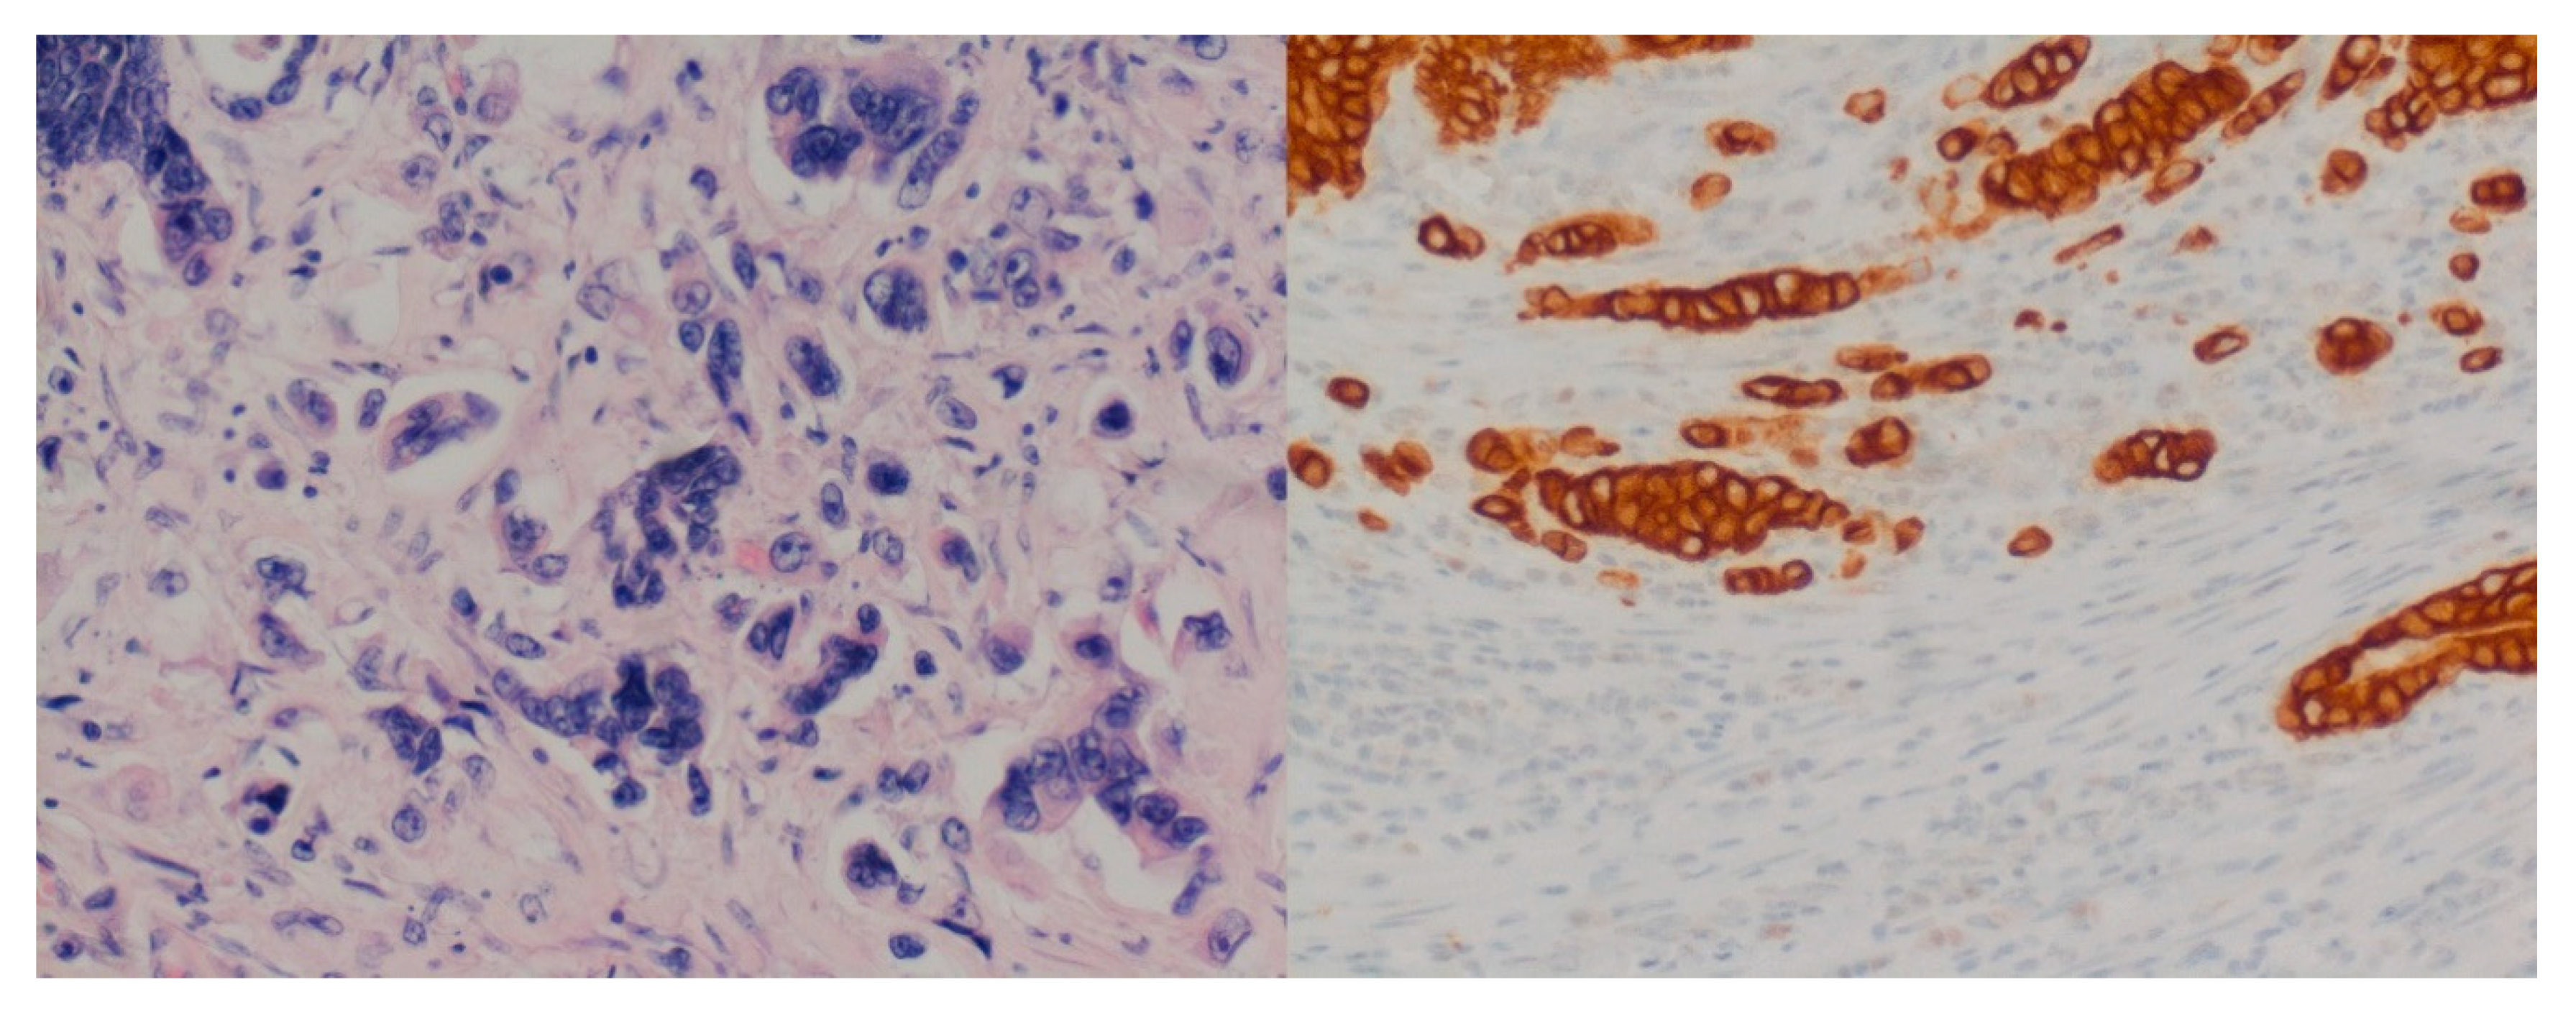

Interobserver Variability in the Assessment of Tumor Budding in pT 3/4 Colon Cancer: Improvement by Supporting Immunohistochemistry?

2. Material and Methods